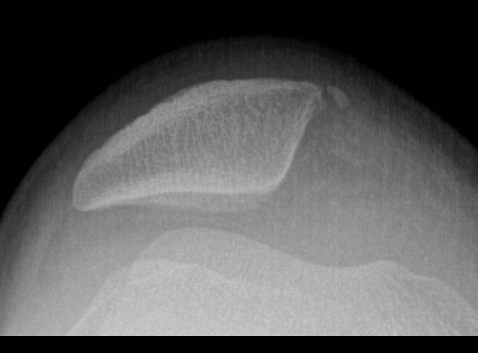

Bony MPFL avulsion

Patella subluxation

Patella should be well engaged in groove

Central ridge should lie at or medial to bisector of the trochlea groove

Patella well engaged in groove versus laterally subluxed patella